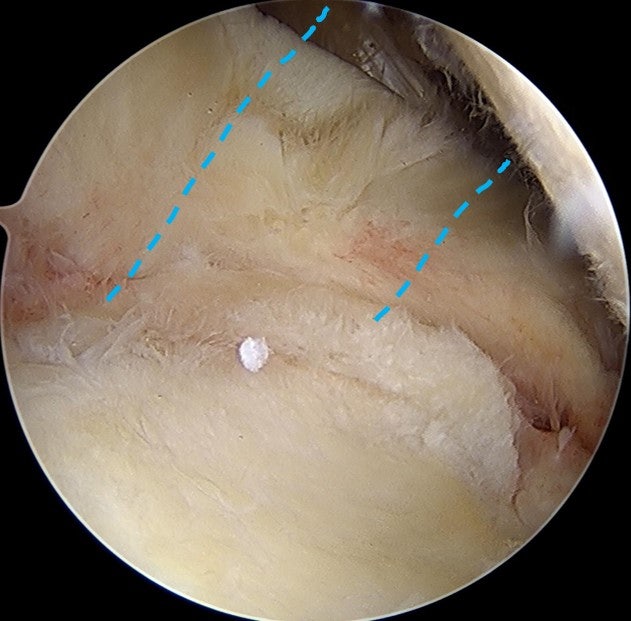

수술을 원래 계획했던 대로 allomend 를 이용하여 회전근개 봉합술 및 봉합술을 시행하였습니다. 수술 직후 MRI 영상으로 확인해 보았습니다.